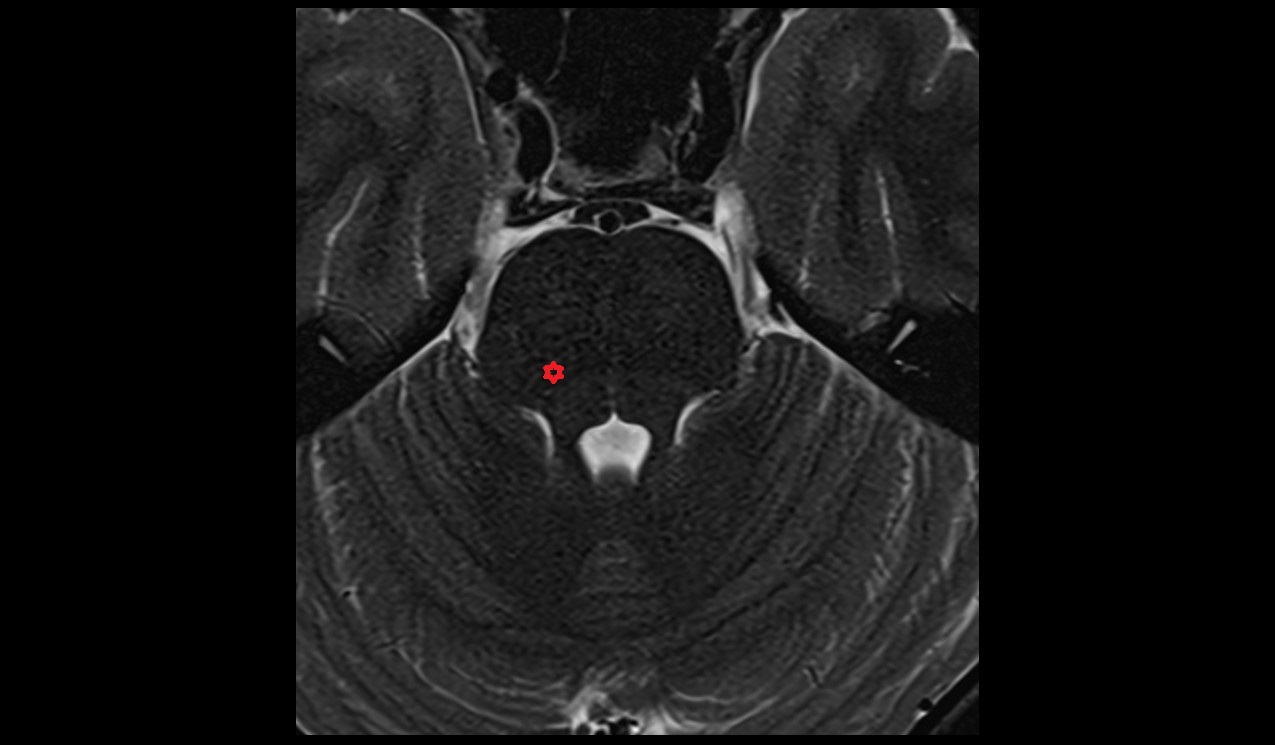

- Peripheral zone of prostate

- Anterior Fibromuscular Stroma of prostate

- Central zone of prostate

- Transitional zone of prostate